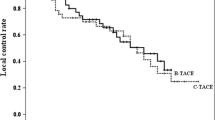

Measurement of BOASP and selective B-TACE were successfully performed in all 43 treatments. The dose of lipiodol ranged 0.5–10 mL (4.5 ± 3.5). The contrast material did not stay, but the arterial flow beyond the occluded portion was maintained on DSA and fluoroscopy in all treatments even after the balloon was inflated. At the beginning of LE infusion, pulsatile flow of the LE droplets into vessels supplying the HCC nodule and those supplying the liver parenchyma was noted in all 43 treatments. After LE droplets reached the peripheral thin vessels supplying the nontumorous liver parenchyma, two flow patterns were observed. The LE inflow into the nontumorous liver parenchyma ceased after the peripheral thin vessels were filled with LE in 39 treatments (group 1) (Figs. 2, 3) but did not cease in four treatments (group 2) (Fig. 4). In all 43 treatments, the LE droplets continued to flow into the HCC nodule. Thus, LE accumulation in the HCC nodule was dense in group 1 (Figs. 2, 3) but not in group 2 (Fig. 4). The BOASP in group 1 was 33.8 ± 12.8 mmHg (range 13–64) and that in group 2 was 92.3 ± 7.4 mmHg (range 83–100). The BOASP in group 1 was lower than that in group 2, with a statistically significant difference (p = 0.00004, Welch’s t test) (Fig. 5). The LECHL ratio was 18.3 ± 13.9 (range 2.9–54.2) in group 1 and 2.6 ± 1.1 (range 1.7–4.2) in group 2. There was a statistically significant difference between the groups (p = 0.000034, Welch’s t test) (Fig. 6).

Scatter diagrams of BOASP. The small symbols represent treatments in which dense LE accumulation in HCC was present (n = 39, group 1), and large symbols represent those in which no dense LE accumulation was present (n = 4, group 2). The symbols on the left side represent treatments in which collateral artery was observed (n = 19, group A), and those on the right side represent those in which no collateral artery was observed (n = 24, group B). There were statistically significant differences in BOASP between groups 1 and 2 (33.8 ± 12.8 mmHg vs. 92.3 ± 7.4 mmHg, p = 0.00004, Welch’s t test) and between groups A and B (51.3 ± 23.8 mmHg vs. 29.8 ± 12.7 mmHg, p = 0.001, Welch’s t test)